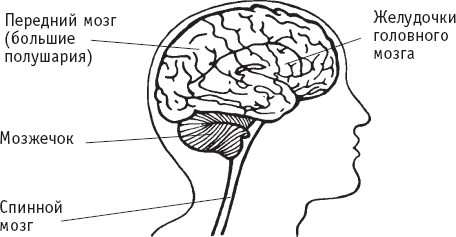

Так как головной и спинной мозг – жизненно важные и чувствительные органы, они надежно защищены от повреждений. Во-первых, череп и позвоночник окружают соответственно головной и спинной мозг прочной костной тканью. Во-вторых, мозг покрыт плотной внешней оболочкой, состоящей из трех слоев. Эти слои защищают и помогают питать нервную ткань (нейроны) головного и спинного мозга. В-третьих, прозрачная жидкость, называемая цереброспинальной, или спинномозговой, циркулирует вокруг и внутри головного и спинного мозга, создавая жидкую прокладку, которая поддерживает эти органы и смягчает удары.

Спинномозговая жидкость образуется в полостях мозга, называемых желудочками. Желудочки выстланы кровеносными сосудами; жидкость и другие элементы крови фильтруются в желудочки, образуя спинномозговую жидкость. Возникнув в желудочках, спинномозговая жидкость циркулирует до тех пор, пока снова не впитается в кровь.

Головной мозг состоит из отделов; каждый отдел отвечает за специфическую функцию. Три главные части головного мозга – передний мозг (большие полушария), мозжечок и ствол мозга.

Мозжечок расположен ниже полушарий, в задней части головного мозга. Он также состоит из правого и левого полушарий. Мозжечок координирует мышечные движения и равновесие, а также получает сенсорные импульсы от слуховых, зрительных и тактильных рецепторов.

Ствол мозга соединяет головной мозг со стволом спинного мозга. Черепные нервы, проводящие сенсорные и двигательные импульсы, начинаются в стволе мозга. К стволу мозга относятся таламус, гипоталамус, варолиев мост и продолговатый мозг. Эти структуры регулируют многие автоматические функции организма, включая ритм сердца и дыхания, температуру тела, кровяное давление, основные рефлексы, некоторые эмоциональные реакции, а также контролируют выделение гормонов.

Строение головного мозга